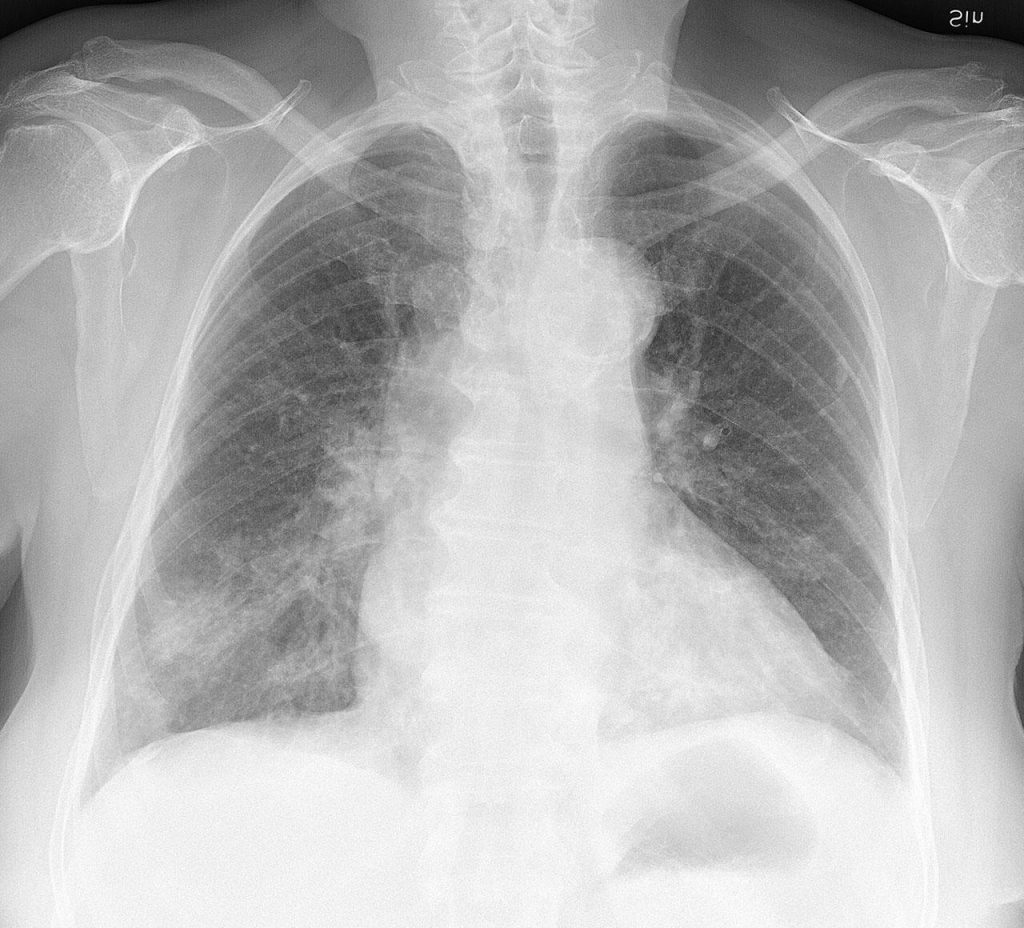

ส่วนสำคัญที่ไม่สามารถอธิบายจากรหัสพันธุกรรมของไวรัสเท่านั้นเป็นกลไกเหนือยีน (epigenetics) และเป็นตัวกำหนดตำแหน่งแห่งที่ ที่ไวรัสสามารถอยู่ได้โดยบรรพบุรุษของโคโรนาจะอยู่ในลำไส้ และค่อยๆปรับเปลี่ยนมาอยู่ในระบบทางเดินหายใจจนกระทั่งถึงถุงลมและพัฒนาเข้าเลือดรวมกระทั่งถึงเม็ดเลือดขาว ทั้งนี้เป็นการปรับเปลี่ยนเพื่อให้สู้กับระบบปกป้องไวรัสของร่างกายของเนื้อเยื่อนั้นๆ คือ ZAP หรือ Zinc finger antiviral protein และ APOBEC3G ที่มีประสิทธิภาพมากในปอด เม็ดเลือดขาว